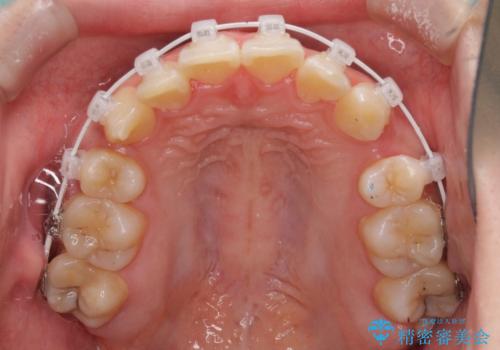

インビザラインが続けられない ワイヤー矯正での抜歯矯正 その1

- 八重歯やデコボコをインビザラインで治療したいとのことで来院された患者様です。

インビザライン単体で治療を行うには叢生が強いと判断されたため、事前にワイヤー装置で抜歯矯正を行い、ある程度改善してからインビザラインにて仕上げていくこととしました。